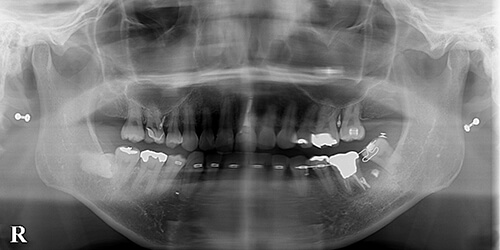

【治療後】

約2年かかりましたが、ようやく目的の位置まで移動することが出来ました。十分に保定後、ミニインプラントは除去致しました。上顎と違って、下顎の8番(親知らず)の部分的矯正は、このケースのようにかなり大変な場合もあります。

しかし、生活歯として使っていけるという圧倒的メリットもあるため、治療期間を除いては、抜歯再植よりもメリットが多い治療法だと思われます。

- 【治療期間】約2年

- 【治療費】約30万円

- 【一般的なリスクや副作用】歯根尖で3cm以上動かす治療なので、時間がかかりました。複雑な矯正器具を付け替えていくので、治療中の咀嚼時等に不快感はあるかと思います。

時間はかかりますが、満足度の高い治療かと思います。